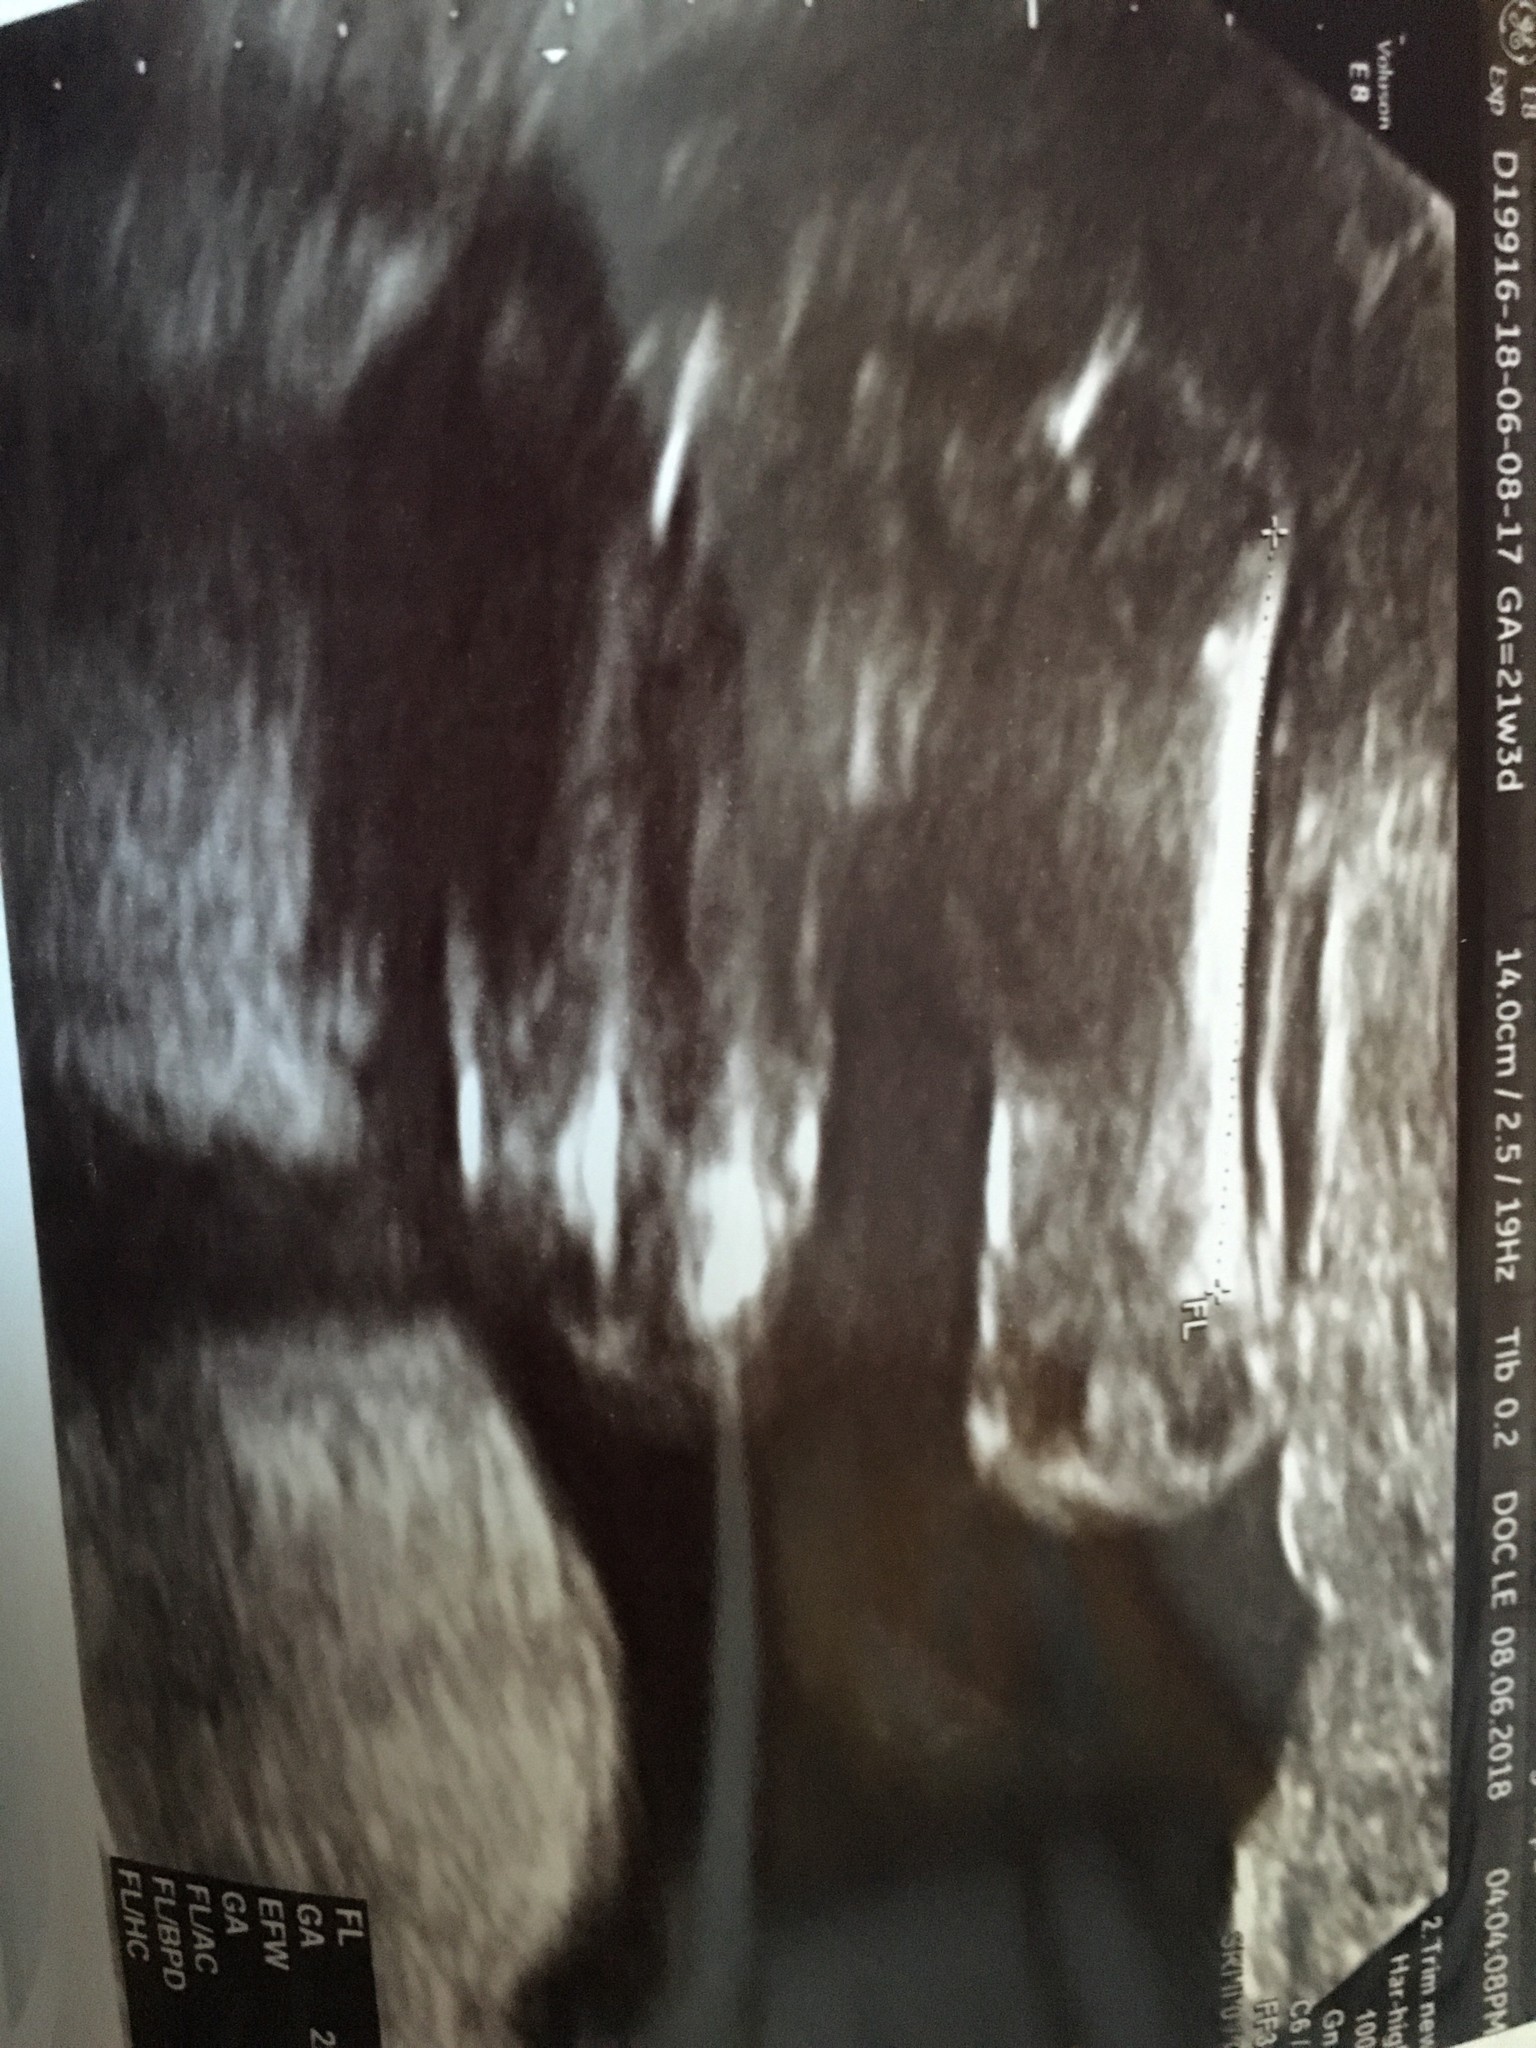

Ja już po badaniu połówkowym. Synek 21+2 z OM waga 447gr, wszystko Ok, posprawdzała wszystko dokładnie i dosyć długo więc jestem zadowolona, zdjęć dostałam chyba z 15 W gabinecie byłam godzinę. Jedyne zastrzeżenie było do długości szyjki 2,67cm. Znowu mam brać luteinę 2*1 i przyjść na kontrole za 2 tyg. Być może dziś miałam taka szyjkę bo spędziłam w aucie 3h i może dziecko tak napierało na ta szyjkę... zobaczymy. Najważniejsze że mały jest zdrowy